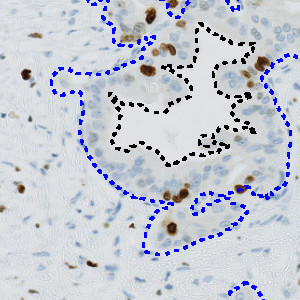

Automatic outline of tumor regions.

The APP can also be used in a more advanced workflow, including automatic tumor detection and hotspot analysis (Figure 1-5). In this setup, tumor regions are identified automatically from cytokeratin stained slides (e.g. PCK) using the APP “20002 – PCK VDS, Tumor Detection”. The APP “10114 – Hot Spot” is used to generate a heatmap to identify a hot spot containing, e.g. 100 cells and the proliferative index is reported for both the entire tumor region and the hot spot.